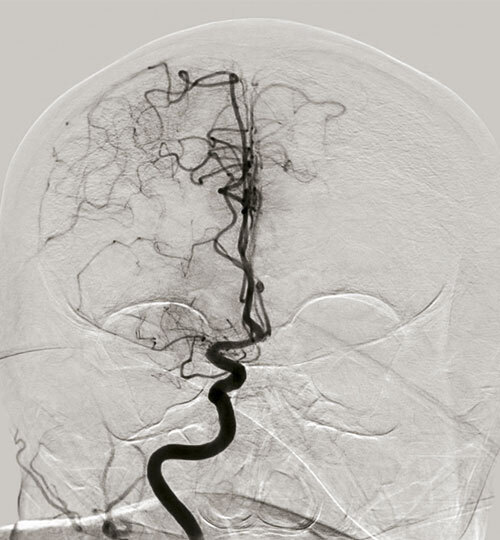

Mazighi M. Recanalisation après une ischémie cérébrale.  Rev Prat 2020;70(6);626-8.